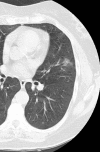

Results: A nonsolid nodule was identified in 2392 (4.2%) of 57,496 baseline screenings, and pathologic pursuit led to the diagnosis of 73 cases of adenocarcinoma. A new nonsolid nodule was identified in 485 (0.7%) of 64,677 annual repeat screenings, and 11 had a diagnosis of stage I adenocarcinoma; none were in nodules 15 mm or larger in diameter. Nonsolid nodules resolved or decreased more frequently in annual repeat than in baseline rounds (322 [66%] of 485 vs 628 [26%] of 2392, P < .0001). Treatment of the cases of lung cancer was with lobectomy in 55, bilobectomy in two, sublobar resection in 26, and radiation therapy in one. Median time to treatment was 19 months (interquartile range [IQR], 6-41 months). A solid component had developed in 22 cases prior to treatment (median transition time from nonsolid to part-solid, 25 months). The lung cancer-survival rate was 100% with median follow-up since diagnosis of 78 months (IQR, 45-122 months).

Conclusion: Nonsolid nodules of any size can be safely followed with CT at 12-month intervals to assess transition to part-solid. Surgery was 100% curative in all cases, regardless of the time to treatment.